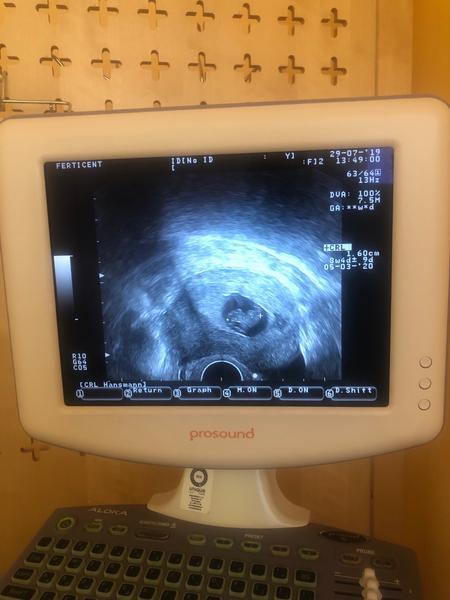

@fialka1318 oficiálne je na fotke písané 8+4 čiže dajme tomu že 8 týždeň . Hej už posledná návšteva . Už buďme len v pn chodiť . Už som objednaná 1.8. A to dievčatko si ja myslím